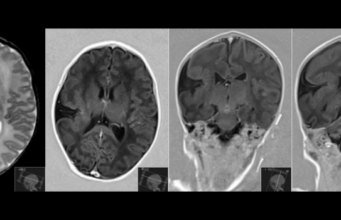

Sindromul opsoclonus-mioclonus

Sindromul opsoclonus-mioclonus - boală neurologică autoimună ce apare ca răspuns la o infecție bacteriană, virală, un vaccin sau o tumoră denumită neuroblastom. Anticorpii ce apar atacă celulele creierului.